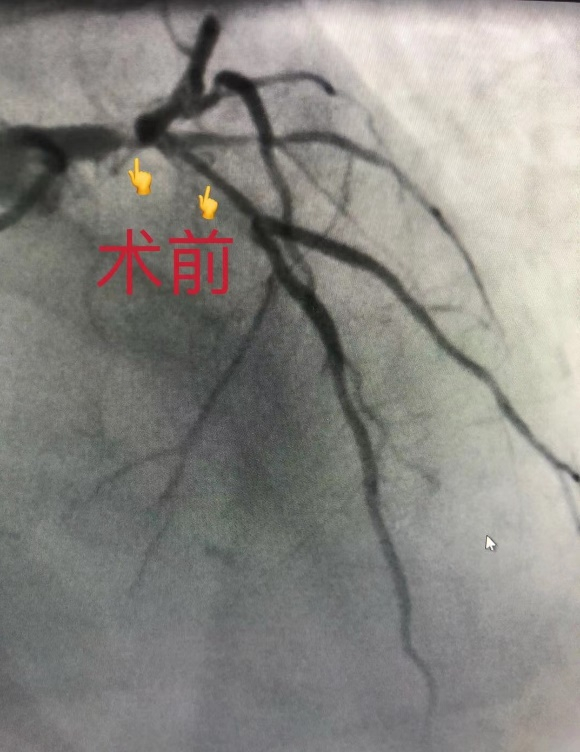

术者翁建新主任医师和黄谦文医生在术中发现,吴先生的心脏血管中:左主干80%被堵塞,左前降支近段90%被堵塞,回旋支及右冠状动脉均80%被堵塞。手术团队依据手术方案,在关键的左主干及左前降支近段病变处植入一枚支架,解除了血管狭窄,使心肌恢复充分的供血。手术团队技术纯熟、准备充分,手术过程十分顺利。

手术前,吴先生被堵塞的心血管;植入支架后,堵塞的心血管开通。